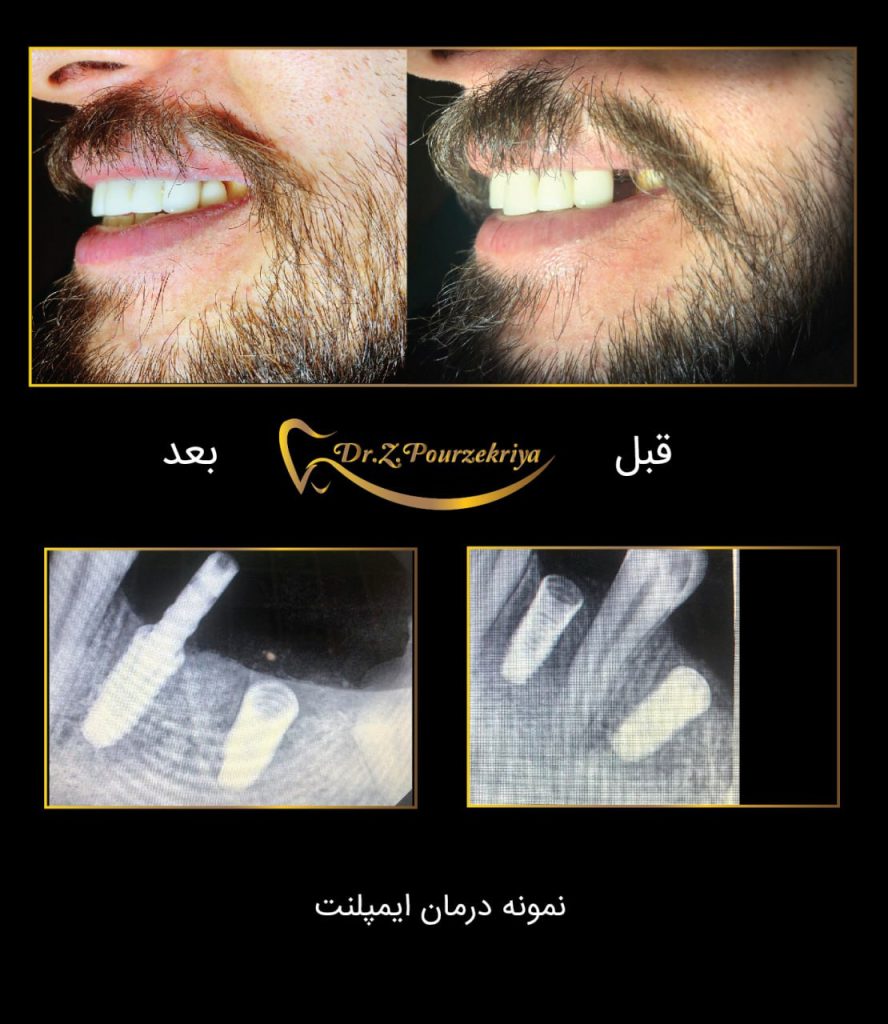

در این روش، بلافاصله پس از کشیدن دندان، ایمپلنت در استخوان فک قرار داده میشود و روکش موقت یا حتی دائمی روی آن نصب میشود.

- کشیدن دندان و قرار دادن ایمپلنت: دندان آسیبدیده کشیده شده و بلافاصله ایمپلنت در استخوان فک قرار میگیرد.

- نصب روکش موقت یا دائمی: پس از قرار دادن ایمپلنت، روکش موقت یا دائمی روی آن نصب میشود.